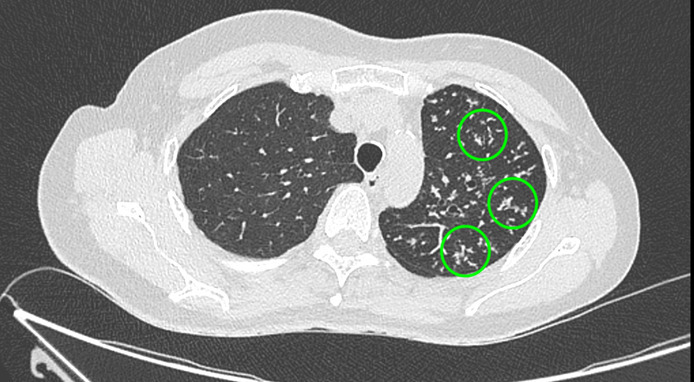

Un scanner thoracique est finalement réalisé devant cette toux chronique et l’altération de l’état général, dont voici quelques coupes :

Figure 4 (Jacques Durin, La Revue du Praticien)

Cercles verts.

Le compte-rendu de radiologie décrit un aspect de pneumopathie lobaire supérieure gauche associée à des micronodules péri-bronchiolaires et des adénopathies médiastino-hilaires calcifiées.